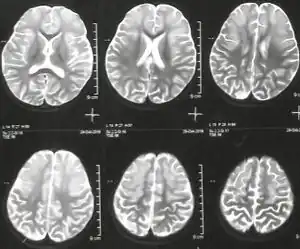

Argininemia is an autosomal recessive urea cycle disorder where a deficiency of the enzyme arginase causes a buildup of arginine and ammonia in the blood. Ammonia, which is formed when proteins are broken down in the body, is toxic if levels become too high; the nervous system is especially sensitive to the effects of excess ammonia.[2][6]

- Microcephaly

- Seizures